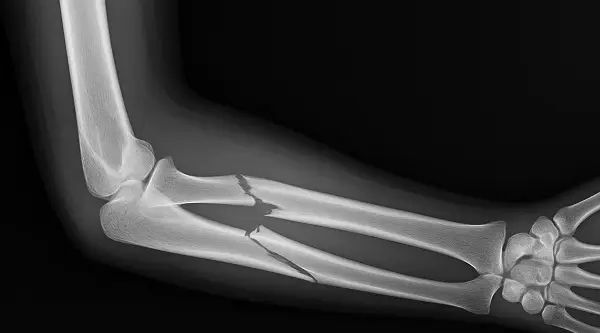

Fracturile diafizare ale oaselor antebratului

Fracturile diafizare ale oaselor antebratului sunt localizate in zona membranei interosoase (sub tuberozitatea bicipitala radiala si deasupra interliniei articulare radio-carpiene, care separa metafiza de diafiza), in urma actiunii agentului traumatic.

In cazul facturii antebratului se poate afirma ca este vorba de o dubla fractura deaorece sunt implicate 2 oase: radiusul si ulna.

Se efectueaza radiografii de fata si profil a intregului antebrat care trebuie sa cuprinda inclusiv articulatiile proximala si distala pentru evidentierea unor eventuale leziuni secundare.

Examenul clinic si radiografia la nivelul antebratului stabileste diagnosticul de certitudine.

Diagnosticul pozitiv se pune pe mobilitatea anormala a segmentului de membru, pe prezenta crepitatiilor osoase si pe imagistica.